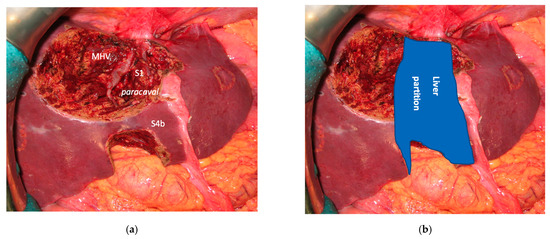

Complete separation of left and right liver is achieved performing a mesohepatectomy involving segments S4 and/or S5/S8 en-bloc with S1 or the paracaval portion only and/or the caudate processus. At the end of liver partition, two independent livers are obtained, with regular inflow and outflow and biliary drainage. The confluence between first-order GPs is always exposed completely (vessel-guided hepatectomy) and the middle hepatic vein (MHV) is usually resected.

3.1. MLP

In all 15 cases planned vessel-guided MLP was successfully carried out. For the surgical approach, a J-shaped laparotomy was used in 13 cases and the xipho-pubic incision in two; no thoraco-abdominal incision was needed. In two cases of MLP performed as the first stage of ALPPS, liver partition was obtained with a single transection line: in one case (FLR = S2/S3/S4b) between a part of S4b and S5 since S4a/S1 were resected in previous e-OSH, in the other case (FLR = S4/S2/Spiegel lobe) the single transection line preserved part of S4a/S4b and the Spiegel lobe. In 11 cases liver partition was obtained with a minor mesohepatectomy: in one case with resection of S4a/S1 partially extended to S5 preserving S4b, in two cases with resection of S1/S4 preserving the Spiegel lobe, in one case with resection of segments S5/S8 extended to the caudate processus of S1 preserving the Spiegel lobe and paracaval portion of S1 and in the other seven cases with anatomic resection of S1/S4 (see Figure 4).

Figure 4. Intraoperative field images of a vessel-guided mesohepatectomy of S1/S4 en-bloc with MHV for liver partition (MLP). MLP is a minor resection (less than 3 adjacent liver segments) inducing a major hepatic scaffold modification transforming the liver into a paired organ. (a) Liver transection lines (yellow dotted lines). (b) Intraoperative view of the two livers. (c) Surgical specimen of S4/S1 en-bloc with MHV corresponding to a volume of 205 mL. Abbreviations: MLP: mesohepatectomy for liver partition; MHV: middle hepatic vein; RHV: right hepatic vein; S: segment; GP: glissonean pedicle; UP: umbilical portion.